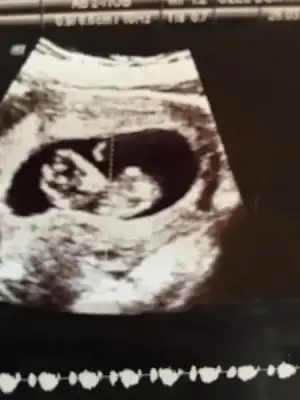

günaydınlar merhaba kızlar. bugün doktora gittik ikili test günümüzdü belki cinsiyeti de öğreniriz dedik ama göstermedi malesef çok uğraştı doktorumuz.durumu iyi dedi ama ense kalınlıgı hakkında pek bişey konuşmadık fotoğraflarımız da böyle :)

Eklentiler

• ultrason2.webp

ultrason2.webp

16,1 KB · Görüntüleme: 86

• ultrasonn.webp

ultrasonn.webp

16,5 KB · Görüntüleme: 77